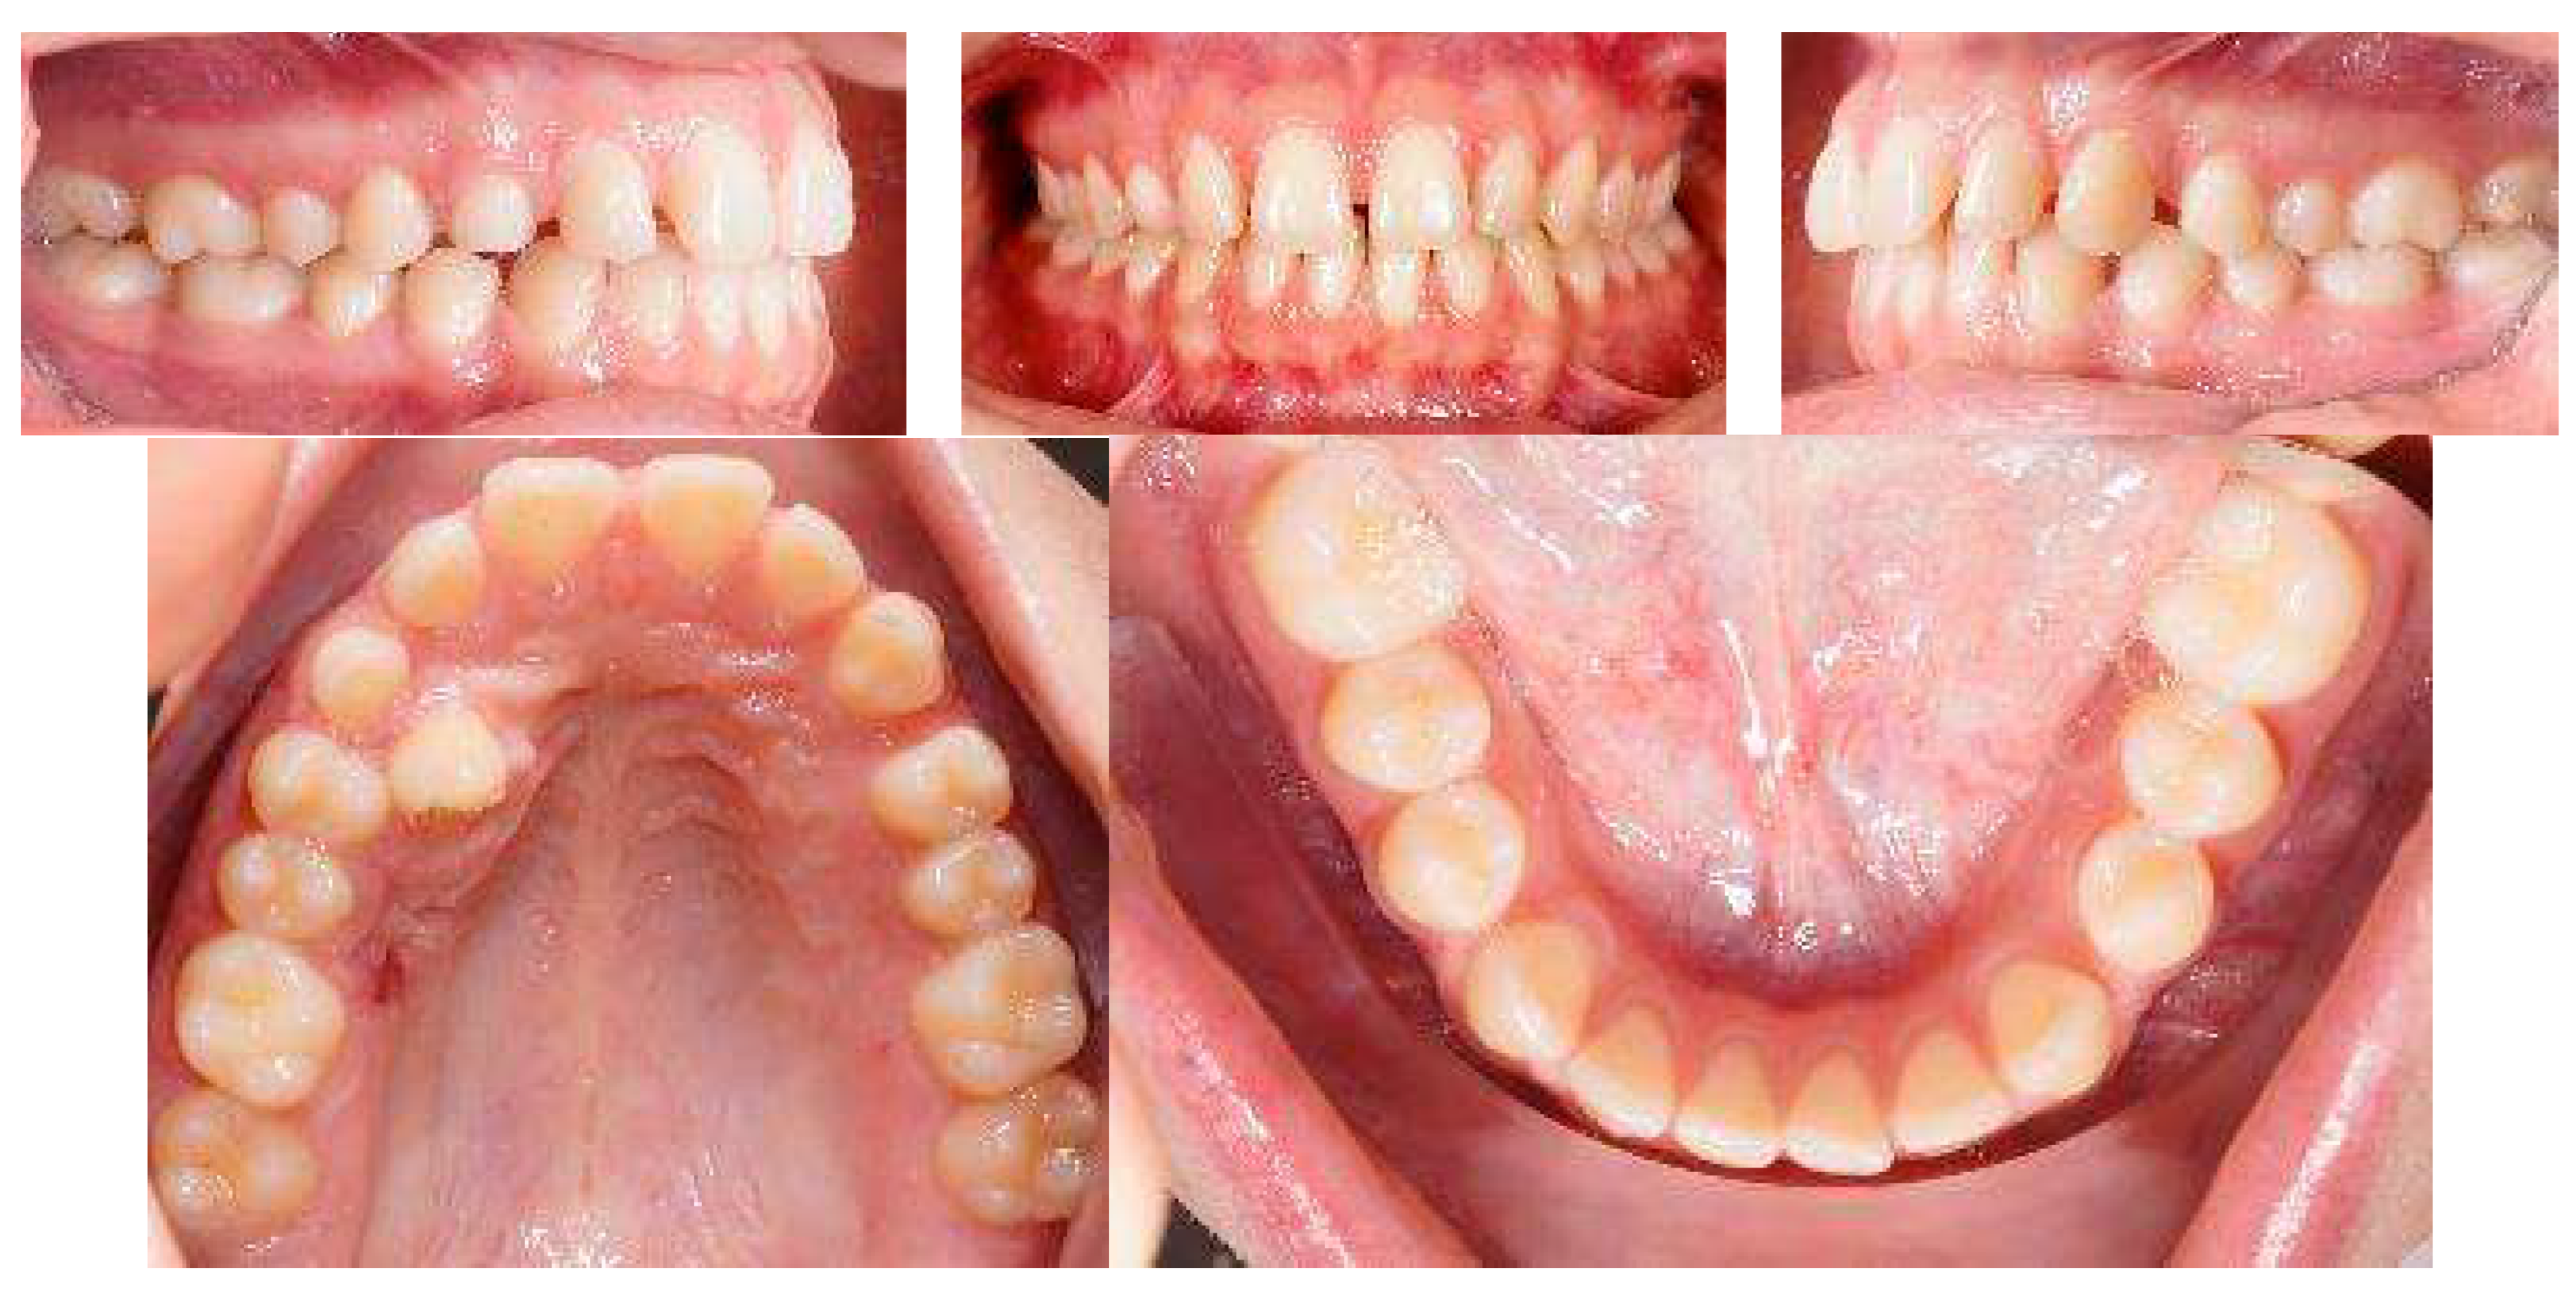

Post-treatment records of the patient successfully treated using a combination of cantilever mechanics with TADs and clear aligners show a control of the facial aesthetics from the frontal and lateral perspectives with a harmonious soft-tissue profile. Final clinical records show good aesthetics and the functional recovery of the upper canines in the arch. A Class I canine relationship was achieved, and overbite and overjet were normalized. The correction of crowding was carried out (Figure 17).

Figure 17.

Post-treatment extraoral and intraoral pictures.

At the end of the treatment, cephalometric radiographs show the good control of the upper and lower inclination. The radiographic evaluation shows an ideal root parallelism and a preserved periodontal health in the canine region (Figure 18). Retention was achieved through Vivera in the upper arch and via a bonded lingual retainer in the lower arch. No TAD failures were observed.

Figure 18.

Final radiographs and landmarks.